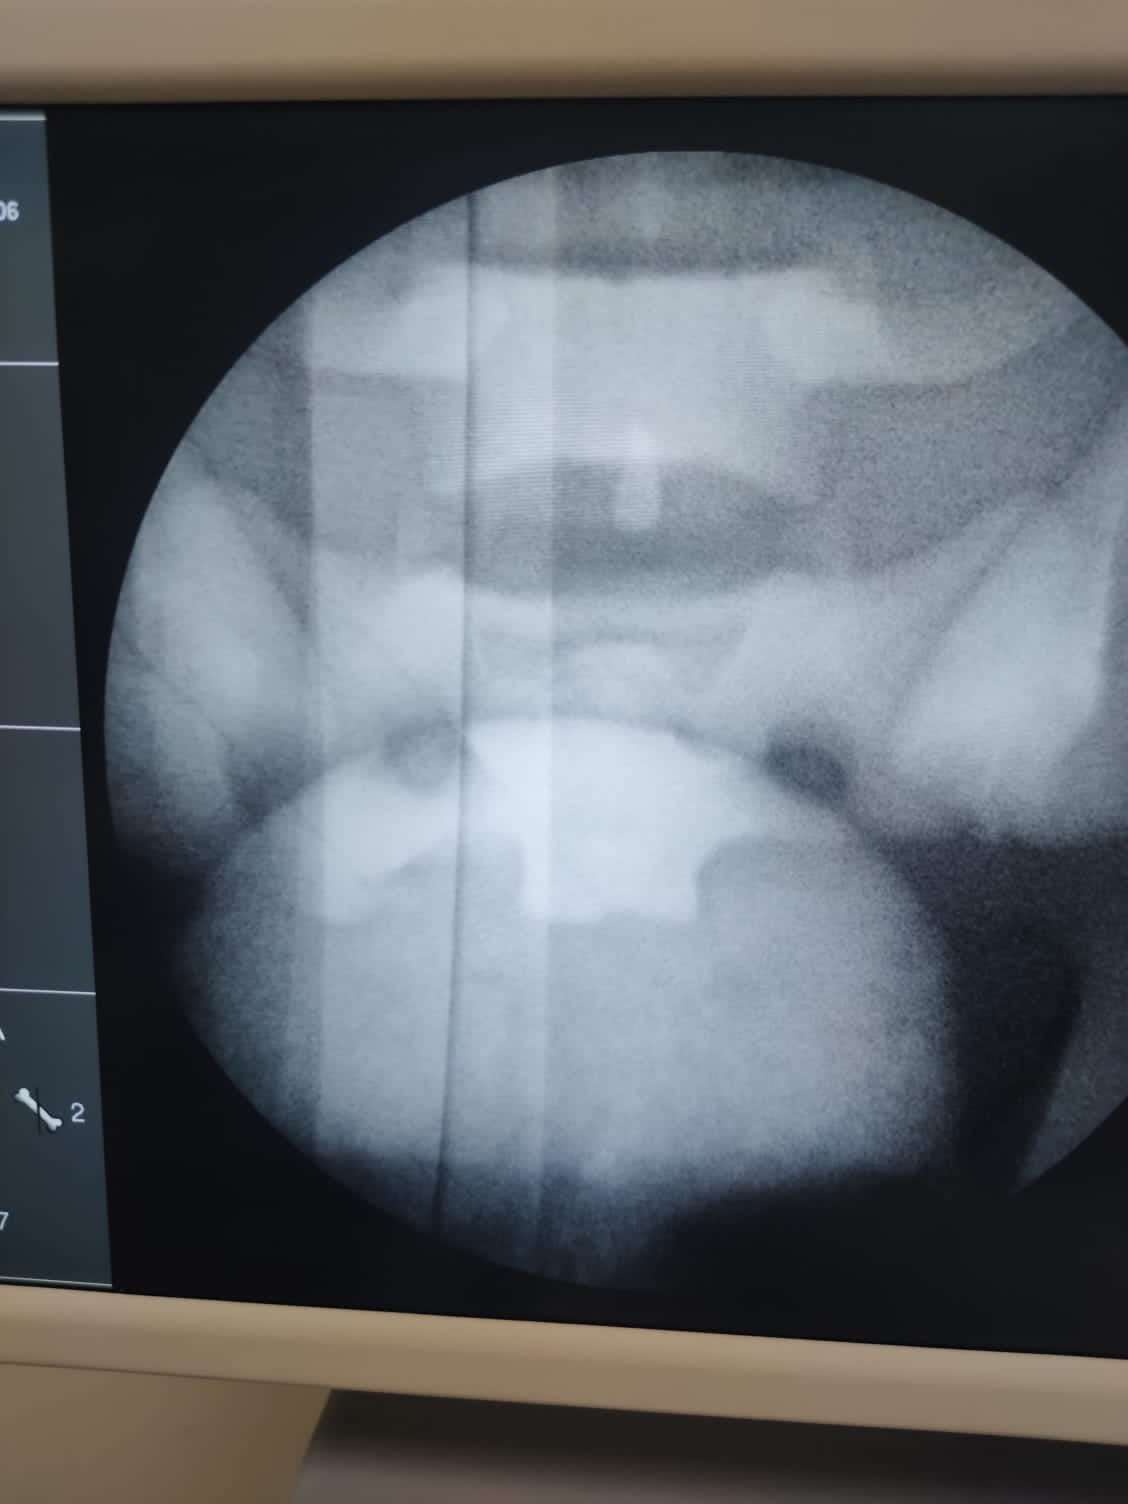

FLUOROSIM LumbarTM

Modular simulator for training procedures by fluoroscopy and ultrasound of Joint blockade, Lumbosacral facets, Caudal Bock Approach represented by 4 lumbar levels and sacriliac joint.